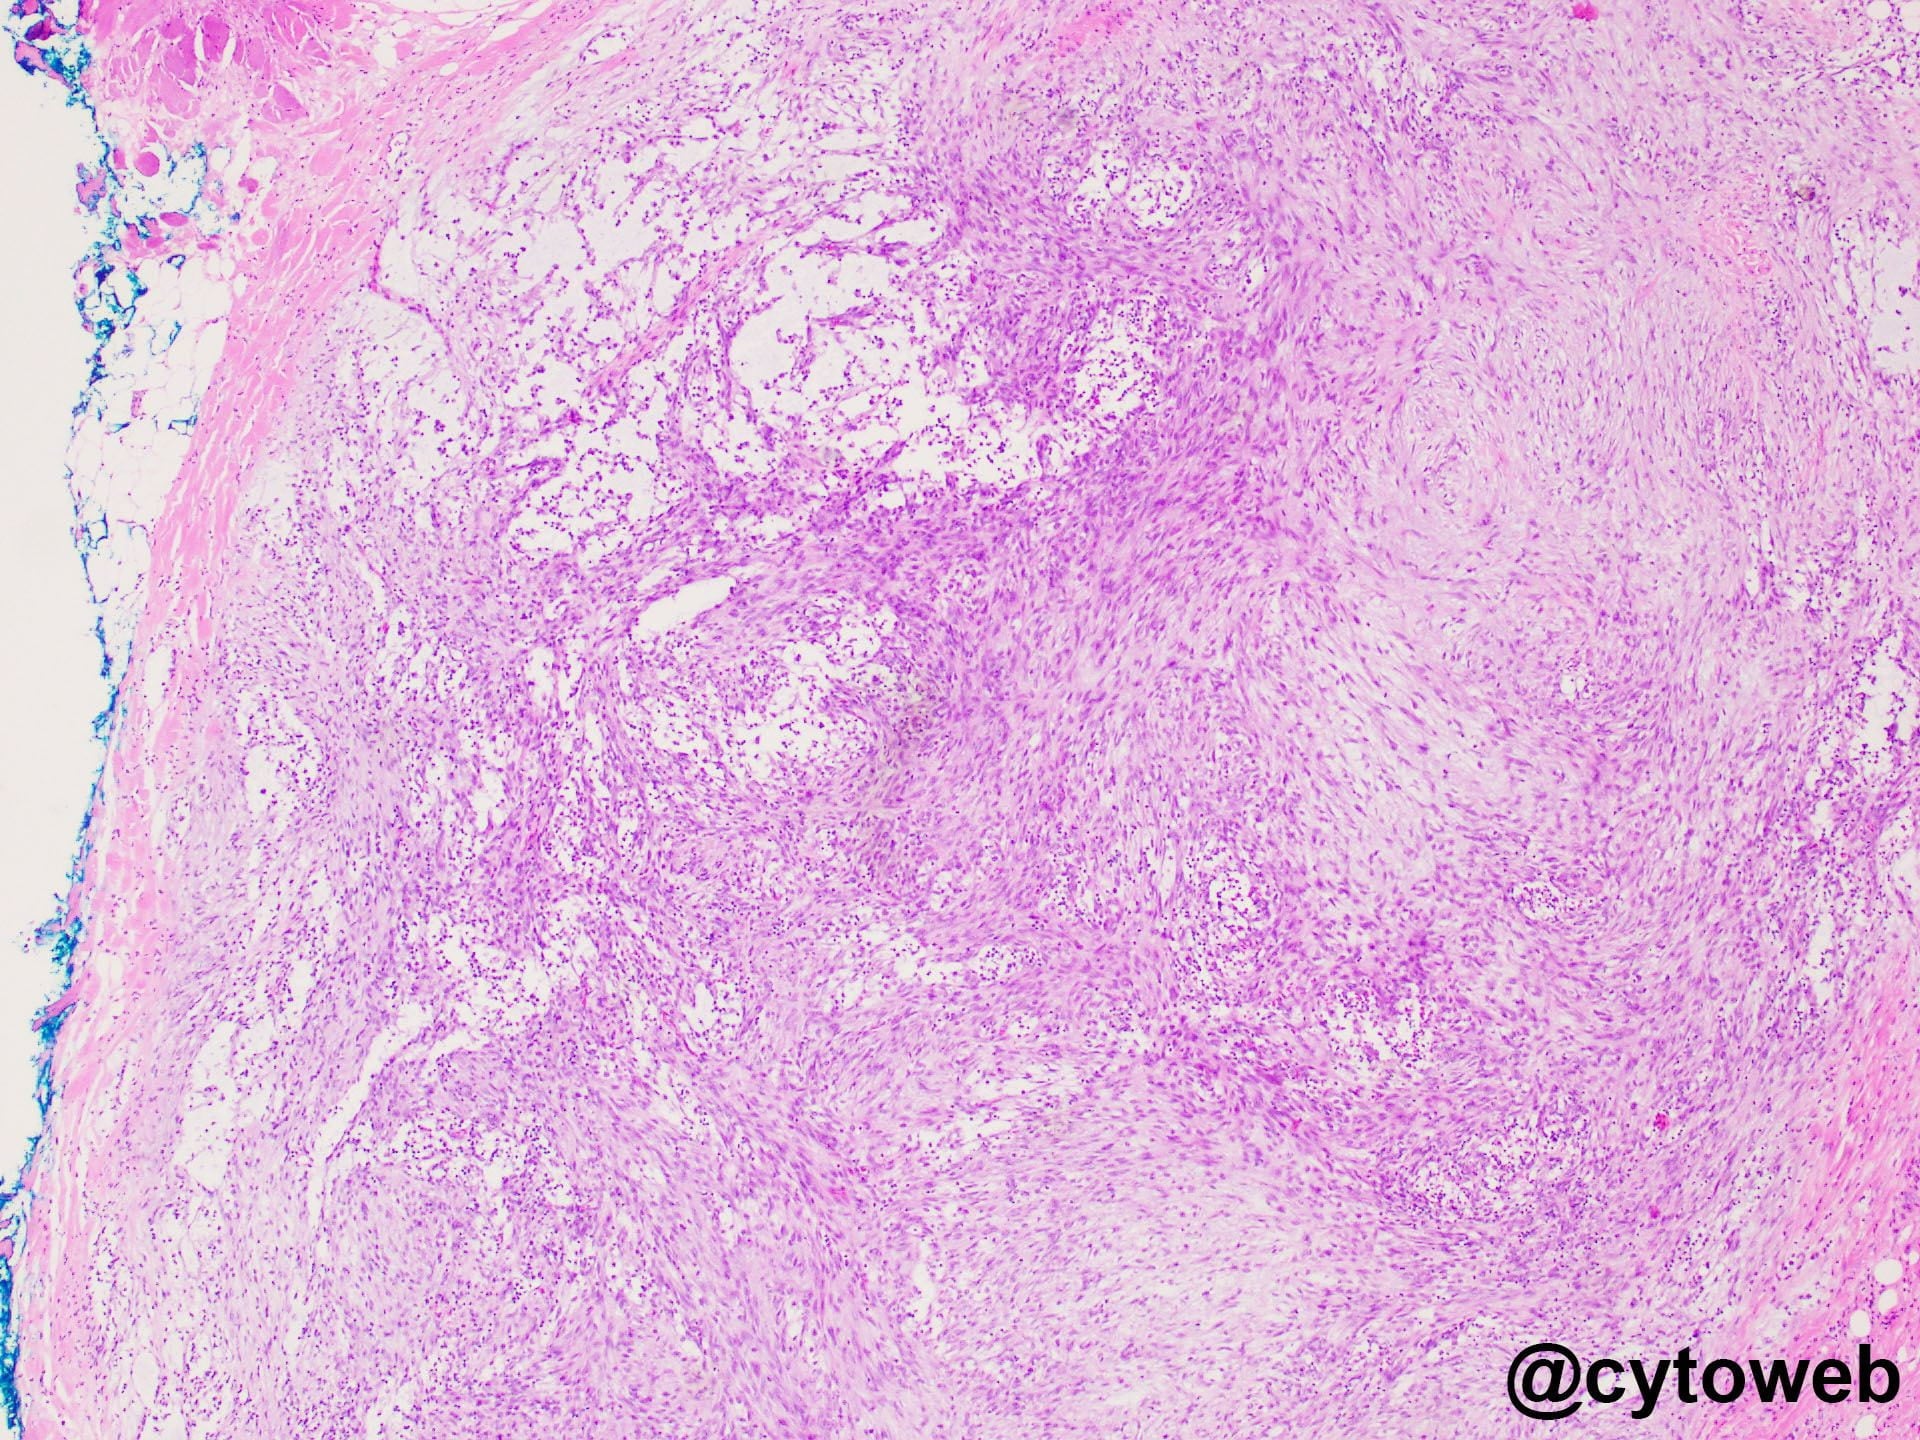

- Nodular fasciitis

- Spindle to stellate cells occurring in clusters and as singly dispersed cells; can be associated with mxyoid stroma

- Cells have abundant cytoplasm and tapering cytoplasmic processes

- Inflammatory cells often seen

- Can have relatively frequent mitoses

- If cell block is available – lesional cells are positive for SMA